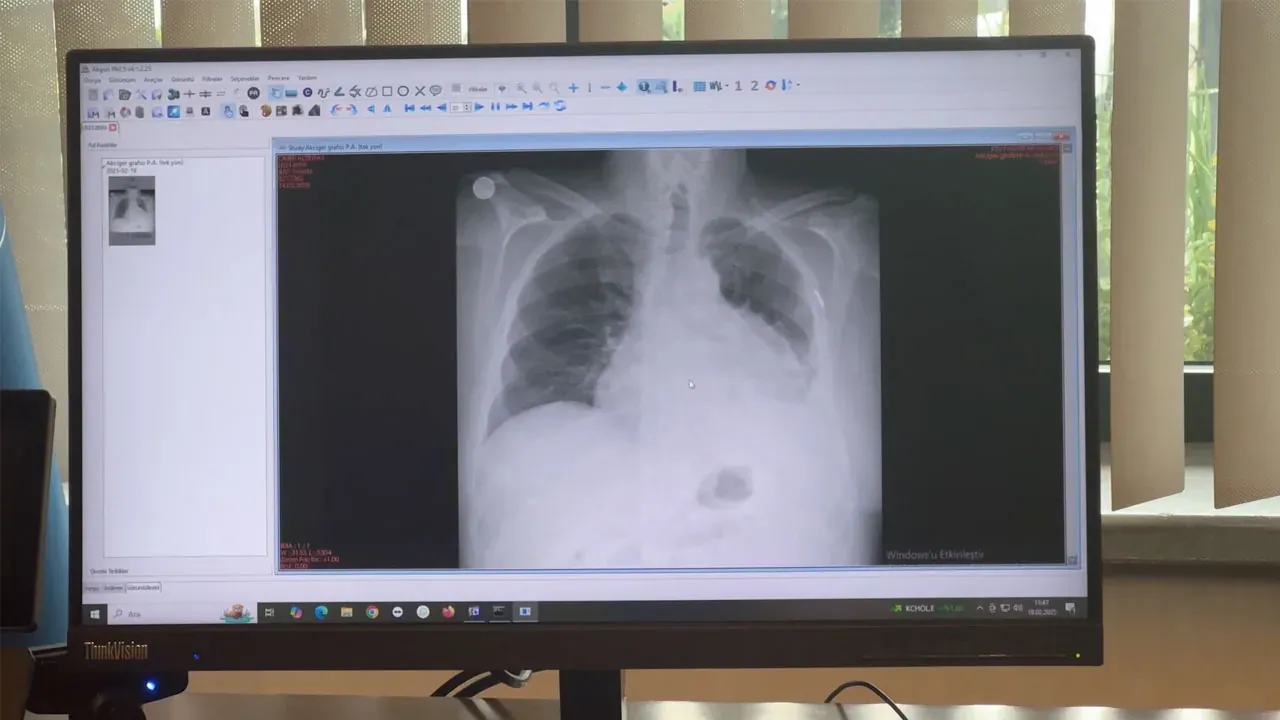

Nefes darlığı ve çarpıntı şikayetleriyle hastaneye başvuran Altıntaş, yapılan tetkikler sonucunda ameliyata alındı. KTÜ Farabi Hastanesi Başhekimi Prof. Dr. Celal Tekinbaş ve ekibi tarafından gerçekleştirilen operasyonda, göğüs boşluğundaki birçok organı etkileyen tümör başarıyla çıkarıldı.

Prof. Dr. Celal Tekinbaş, tümörün sol akciğerin alt bölgesine ve kalp zarına kadar yayıldığını, ayrıca karın içindeki organlara baskı yaptığını açıkladı. Uzun süren operasyonun ardından akciğerin alt lobu, diyafragma ve kalp zarı çıkarılarak yerine suni yamalar yerleştirildi.